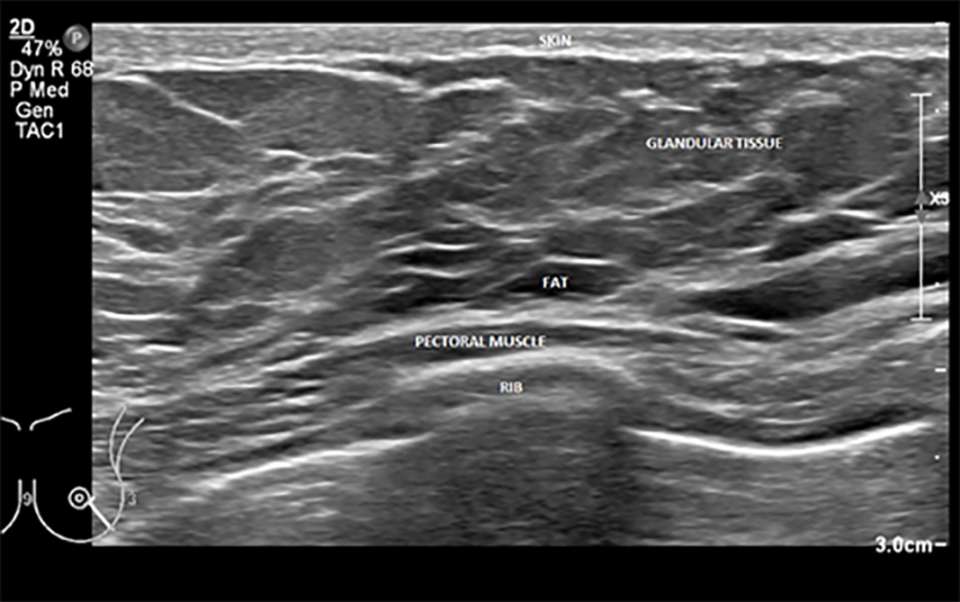

A labeled example of normal breast anatomy on ultrasound can be seen below. Of note, fat in the breast is hypoechoic, unlike ultrasound imaging of fat elsewhere in the body where is it primarily hyperechoic.